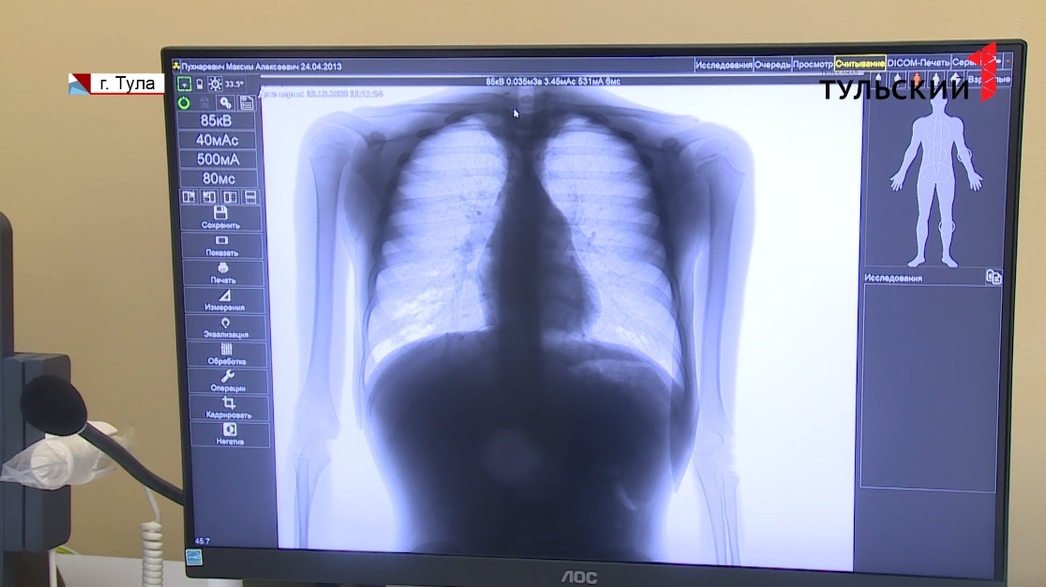

Почему туберкулез перестал быть болезнью маргиналов? Об этом рассказала заведующая туберкулезным отделением для взрослых Тульского областного противотуберкулезного диспансера №1 Ксения Баранова.

По данным Всемирной организации здравоохранения, ежегодно в мире от туберкулёза умирают 1,2 миллиона человек. И то, что болеют им исключительно маргинальные личности раньше действительно было правдой.

Но сейчас туберкулез – социальная болезнь, ведь все люди находятся в контакте друг с другом. Чаще болеют люди со сниженным иммунитетом, с заболеваниями, которые более адаптивны к туберкулезной палочке – сахарный диабет, онкологические заболевания и проблемы с ЖКТ и сердечнососудистой системой.